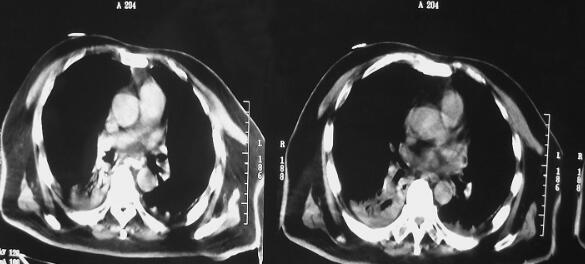

诊治经过:患者入笔者科室后一般情况较差,血压测不出,氧饱和度84%,予以羟乙基淀粉扩容,多巴胺、去甲肾上腺素微泵维持血压,碳酸氢钠纠正酸中毒。立即予以气管插管,呼吸机辅助通气。完善相关检查:CT(图1)结果:①头颅CT平扫未见明显异常;②双下肺肺不张;③双侧胸腔积液;④肝右叶钙化灶。血常规(2月7日):WBC 20.9×109/L,N 94%。心脏彩超(2月8日):左心室舒张末内径61mm,射血分数38%。胸片(图2~图4)诊断:①双侧肺炎;②颈椎术后。先后给予头孢曲松钠和左氧氟沙星、美罗培南和替考拉宁抗感染。因痰培养鲍曼不动杆菌(2月10日),对头孢哌酮-舒巴坦钠敏感,余均耐药,故停用美罗培南,改用头孢哌酮-舒巴坦钠。多次血培养结果提示白念珠菌(2月6日、2月7日、2月9日、2月10日),对氟康唑和伊曲康唑均敏感,因为患者肌酐高,肾功能异常,故给予米卡芬净和氟康唑抗真菌治疗。患者血糖高,2月6日末梢血血糖33.1mmol/L,给予胰岛素强化治疗,但是血糖控制不佳,一直在11mmol/L以上。同时给予化痰、抗炎、保肝、营养神经、调节机体免疫、加强营养、维持内环境稳定、对症支持等治疗。

图3 2月10日胸片